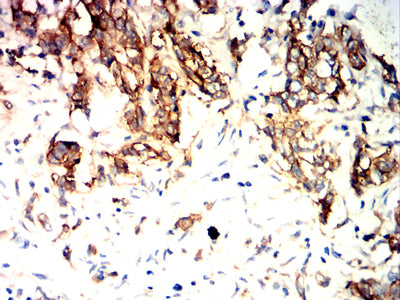

Immunohistochemical analysis of paraffin-embedded human liver cancer tissues using TSPAN8 mouse mAb with DAB staining.

-

Immunohistochemical analysis of paraffin-embedded human rectal cancer tissues using TSPAN8 mouse mAb with DAB staining.

Immunohistochemical analysis of paraffin-embedded human stomach cancer tissues using TSPAN8 mouse mAb with DAB staining.